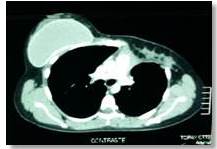

La segunda paciente de 31 años, consultó por tumor en mama izquierda de 7 meses de evolución, como antecedente la paciente se realizó mastoplastia de aumento en los 2 años anteriores, colocándose implantes de silicón sin complicaciones. El examen físico inicial se palpa tumor en cuadrante súpero-interno de 5 cm x 5 cm duro no móvil, adherido a planos profundos no doloroso. En la mamografía no se observan lesiones, la tomografía de tórax con contraste endovenoso reportó prótesis retro-pectorales bilaterales de superficie onduladas, en el área pre-pectoral izquierda existe lesión de 7 cm x 4,5 cm x 4,1 cm para un volumen de 66 cm3, con densidad mixta y predominantemente líquido. En la RMN de mama se observó masa sólida heterogénea de mama izquierda, tamaño de 32 mm x 35 mm x 52 mm, signos de encapsulamiento en prótesis izquierda. La biopsia con aguja gruesa eco-guiada concluye tumor desmoide. Con este diagnóstico se realizó resección local amplia de tumor más retiro de prótesis. La biopsia definitiva reportó tumor de 9 cm x 5,9 cm x 3,5 cm compatible con fibromatosis agresiva extra-abdominal observando patrón de crecimiento infiltrativo, con márgenes negativos para lesión. Posterior a 27 meses de seguimiento la paciente se encuentra libre de enfermedad locorregional y a distancia.